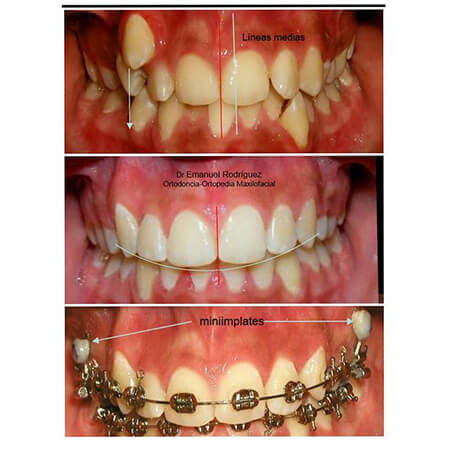

Orthodontic results performed by the dentist Emanuel Rodríguez

Results of orthodontic treatment performed by the orthodontist Emmanuel Rodríguez

Orthodontic results performed by the orthodontist Emmanuel Rodríguez